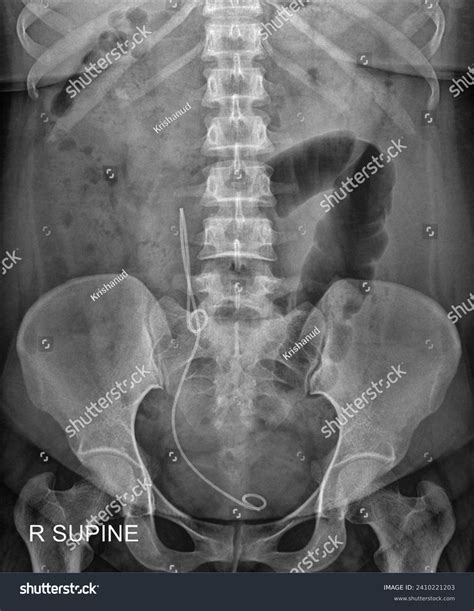

Imaging Tests

Imaging tests, such as ultrasound, CT scan, or MRI, can provide detailed images of the Kub Kidney Ureter Bladder system and help identify abnormalities, such as kidney stones, tumors, or blockages.